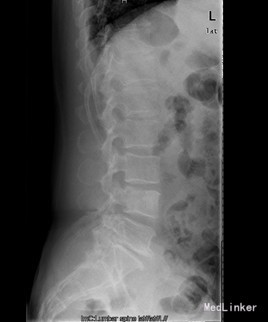

患者男,60岁,因“反复双下肢疼痛麻木4+年,加重伴腰痛4+月”入院。 入院前4+年患者无明显诱因出现右下肢麻木疼痛,呈持续性放射痛,无腰痛及下肢活动受限,4+月前患者无明显诱因出现双下肢反复交替麻木疼痛,呈放射性疼痛,双侧大腿后方小腿外侧及足背感觉麻木,以右侧较重,同时出现腰骶部疼痛,疼痛明显时患者出现跛行步态伴腰部活动受限, 今进一步治疗遂入我院。

查体:腰4、5棘突轻度叩压痛,双侧大腿后外侧小腿外侧及足背感觉功能减退,以右侧明显。 辅查:CT示腰4椎体骨质破坏并增生、硬化改变,以骨质破坏为主,左侧椎旁软组织肿块形成,结核?肿瘤待排。腰4、5腰5骶1椎间盘突出。腰椎退行性变。MRI示腰4椎体骨质破坏,性质?腰4、5腰5骶1椎间盘突出,腰椎退行性变,双侧髂骨信号不均匀,性质?

初步诊断:腰4椎体骨质破坏:结核?肿瘤? 诊疗计划:经前路腰4椎体部分切除,椎管减压,取自体髂骨植骨融合,Antares内固定术